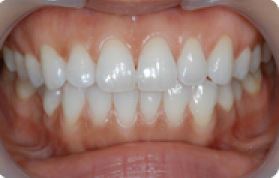

치아교정 세라믹브라켓 전후사례 | 2020.03.06 |